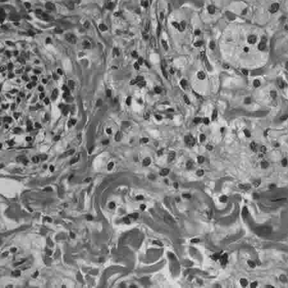

Histologically, ECD differs from Langerhans cell histiocytosis (LCH) in a number of ways. Unlike LCH, ECD does not stain positive for S-100 proteins or Group 1 CD1a glycoproteins, and electron microscopy of cell cytoplasm does not disclose Birbeck granules.[3] Tissue samples show xanthomatous or xanthogranulomatous infiltration by lipid-laden or foamy histiocytes, and are usually surrounded by fibrosis. Bone biopsy is said to offer the greatest likelihood of reaching a diagnosis. In some, there is histiocyte proliferation, and on staining, the section is CD68+ and CD1a-.